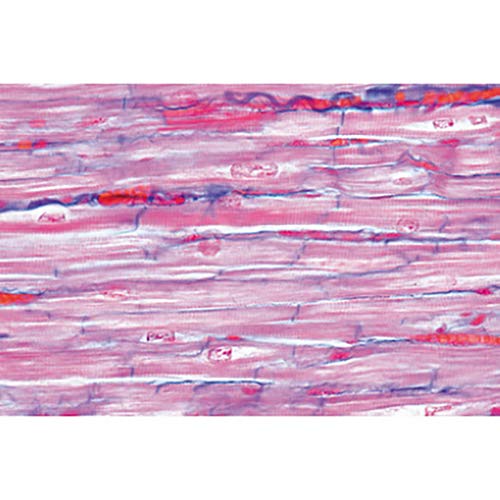

- Heart muscle, human t.s. and l.s. intercalated discs